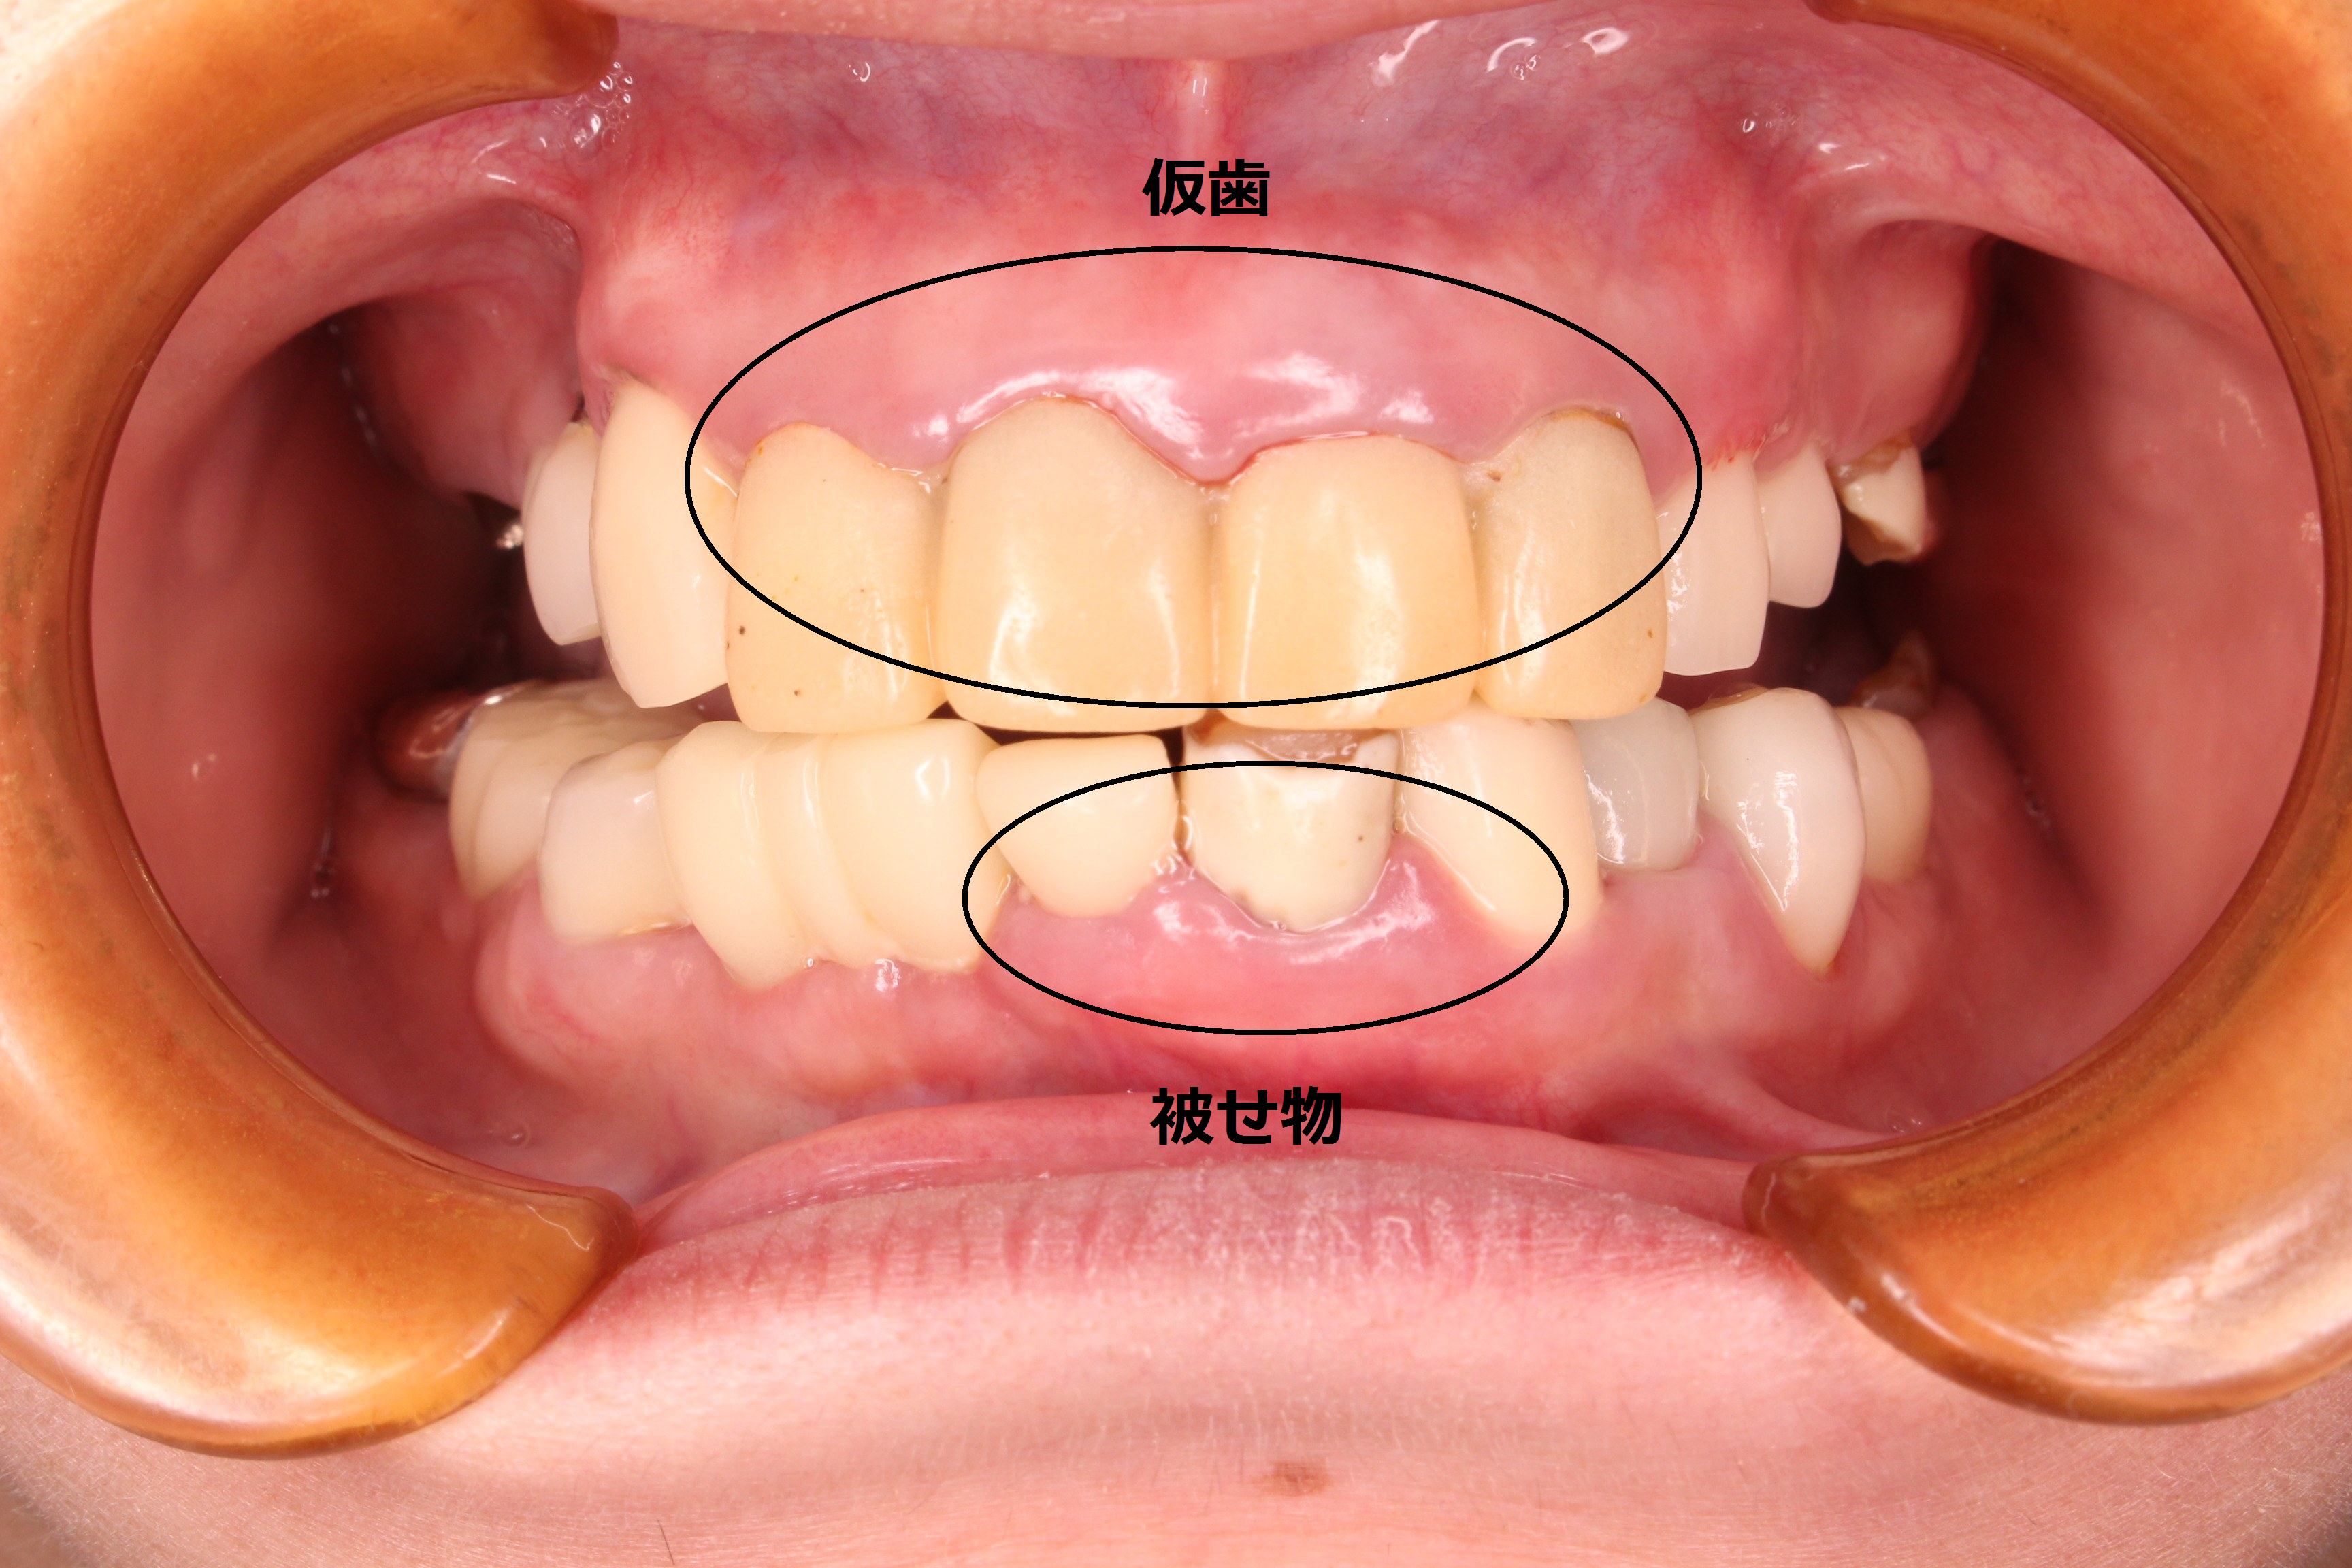

どうにかしたいけど、痛いのはイヤ・・・

こんにちは。 南館歯科クリニックの歯科衛生士の山崎です。 今回ご紹介する症例は、70代女性の方です。 実は以前、歯周治療を他院で行い、その後、上の前歯にきれいな被せ物が装着してありました…

せっかくやるなら、しっかり治したい

こんにちは。南館歯科クリニックの歯科衛生士の山崎です。 今回ご紹介する歯周専門治療のケースは、30代男性の方です。 小学生のお子さんから口臭を指摘されたり、ご自身でも歯肉が下がって歯周病…